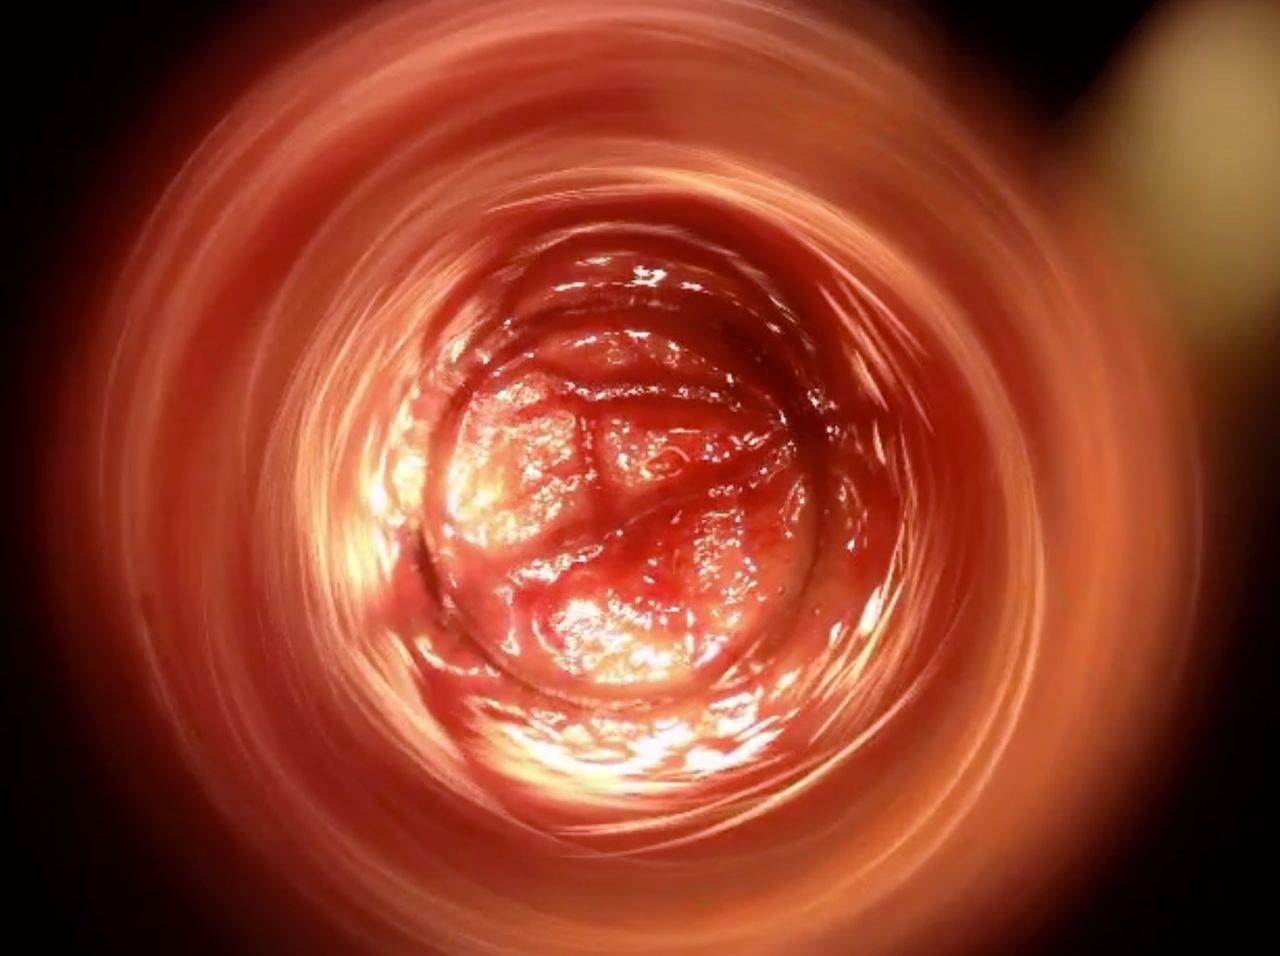

Come Chirurgo Vascolare, sono perfezionata in Proctologia da molti anni, e molti altri ne ho passati direttamente in sala operatoria, praticando l'emorroidectomia con metodo Milligan-Morgan.

Durante la mia esperienza come Chirurgo Protcologo, ho visto personalmente come i trattamenti chirurgici disponibili, benché necessari, fossero comunque abbastanza invasivi per il paziente, specialmente nel decorso post operatorio.

Fortunatamente, negli ultimi anni sono stati messi a punto protocolli non chirurgici molto avanzati, che ho personalmente studiato ed approfondito con molto interesse.

Tra questi, ho cominciato ad utilizzare il trattamento sclerotizzante con scleromousse stabilizzata ad aria sterilizzata, che considero ormai il 'Gold Standard' per il trattamento non invasivo e permanente delle emorroidi patologiche.

Ho quindi attrezzato il mio studio con il moderno Videoproctoscopio Digitale, nonché con avanzate pompe miscelatrici ad aria sterilizzata, in grado di ottenere una scleromousse stabilizzata di grande qualità, perfetta per il trattamento emorroidale.

Grazie a questo protocollo, posso risolvere casi anche molto gravi di prolasso emorroidale, garantendo una risoluzione definitiva in oltre il 95% dei casi clinici.

Il tutto, senza il minimo dolore o disagio per il paziente.